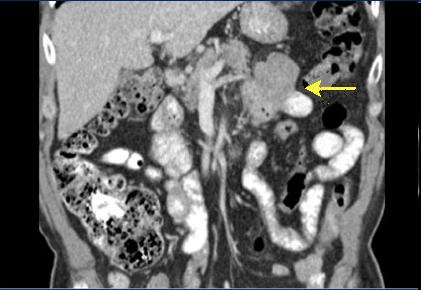

Grand tumeur de GIST a

distal de jejunum . Tumeur en multilobaire extra-luminale

de intestin et calcification . ( fleche jaune ) |